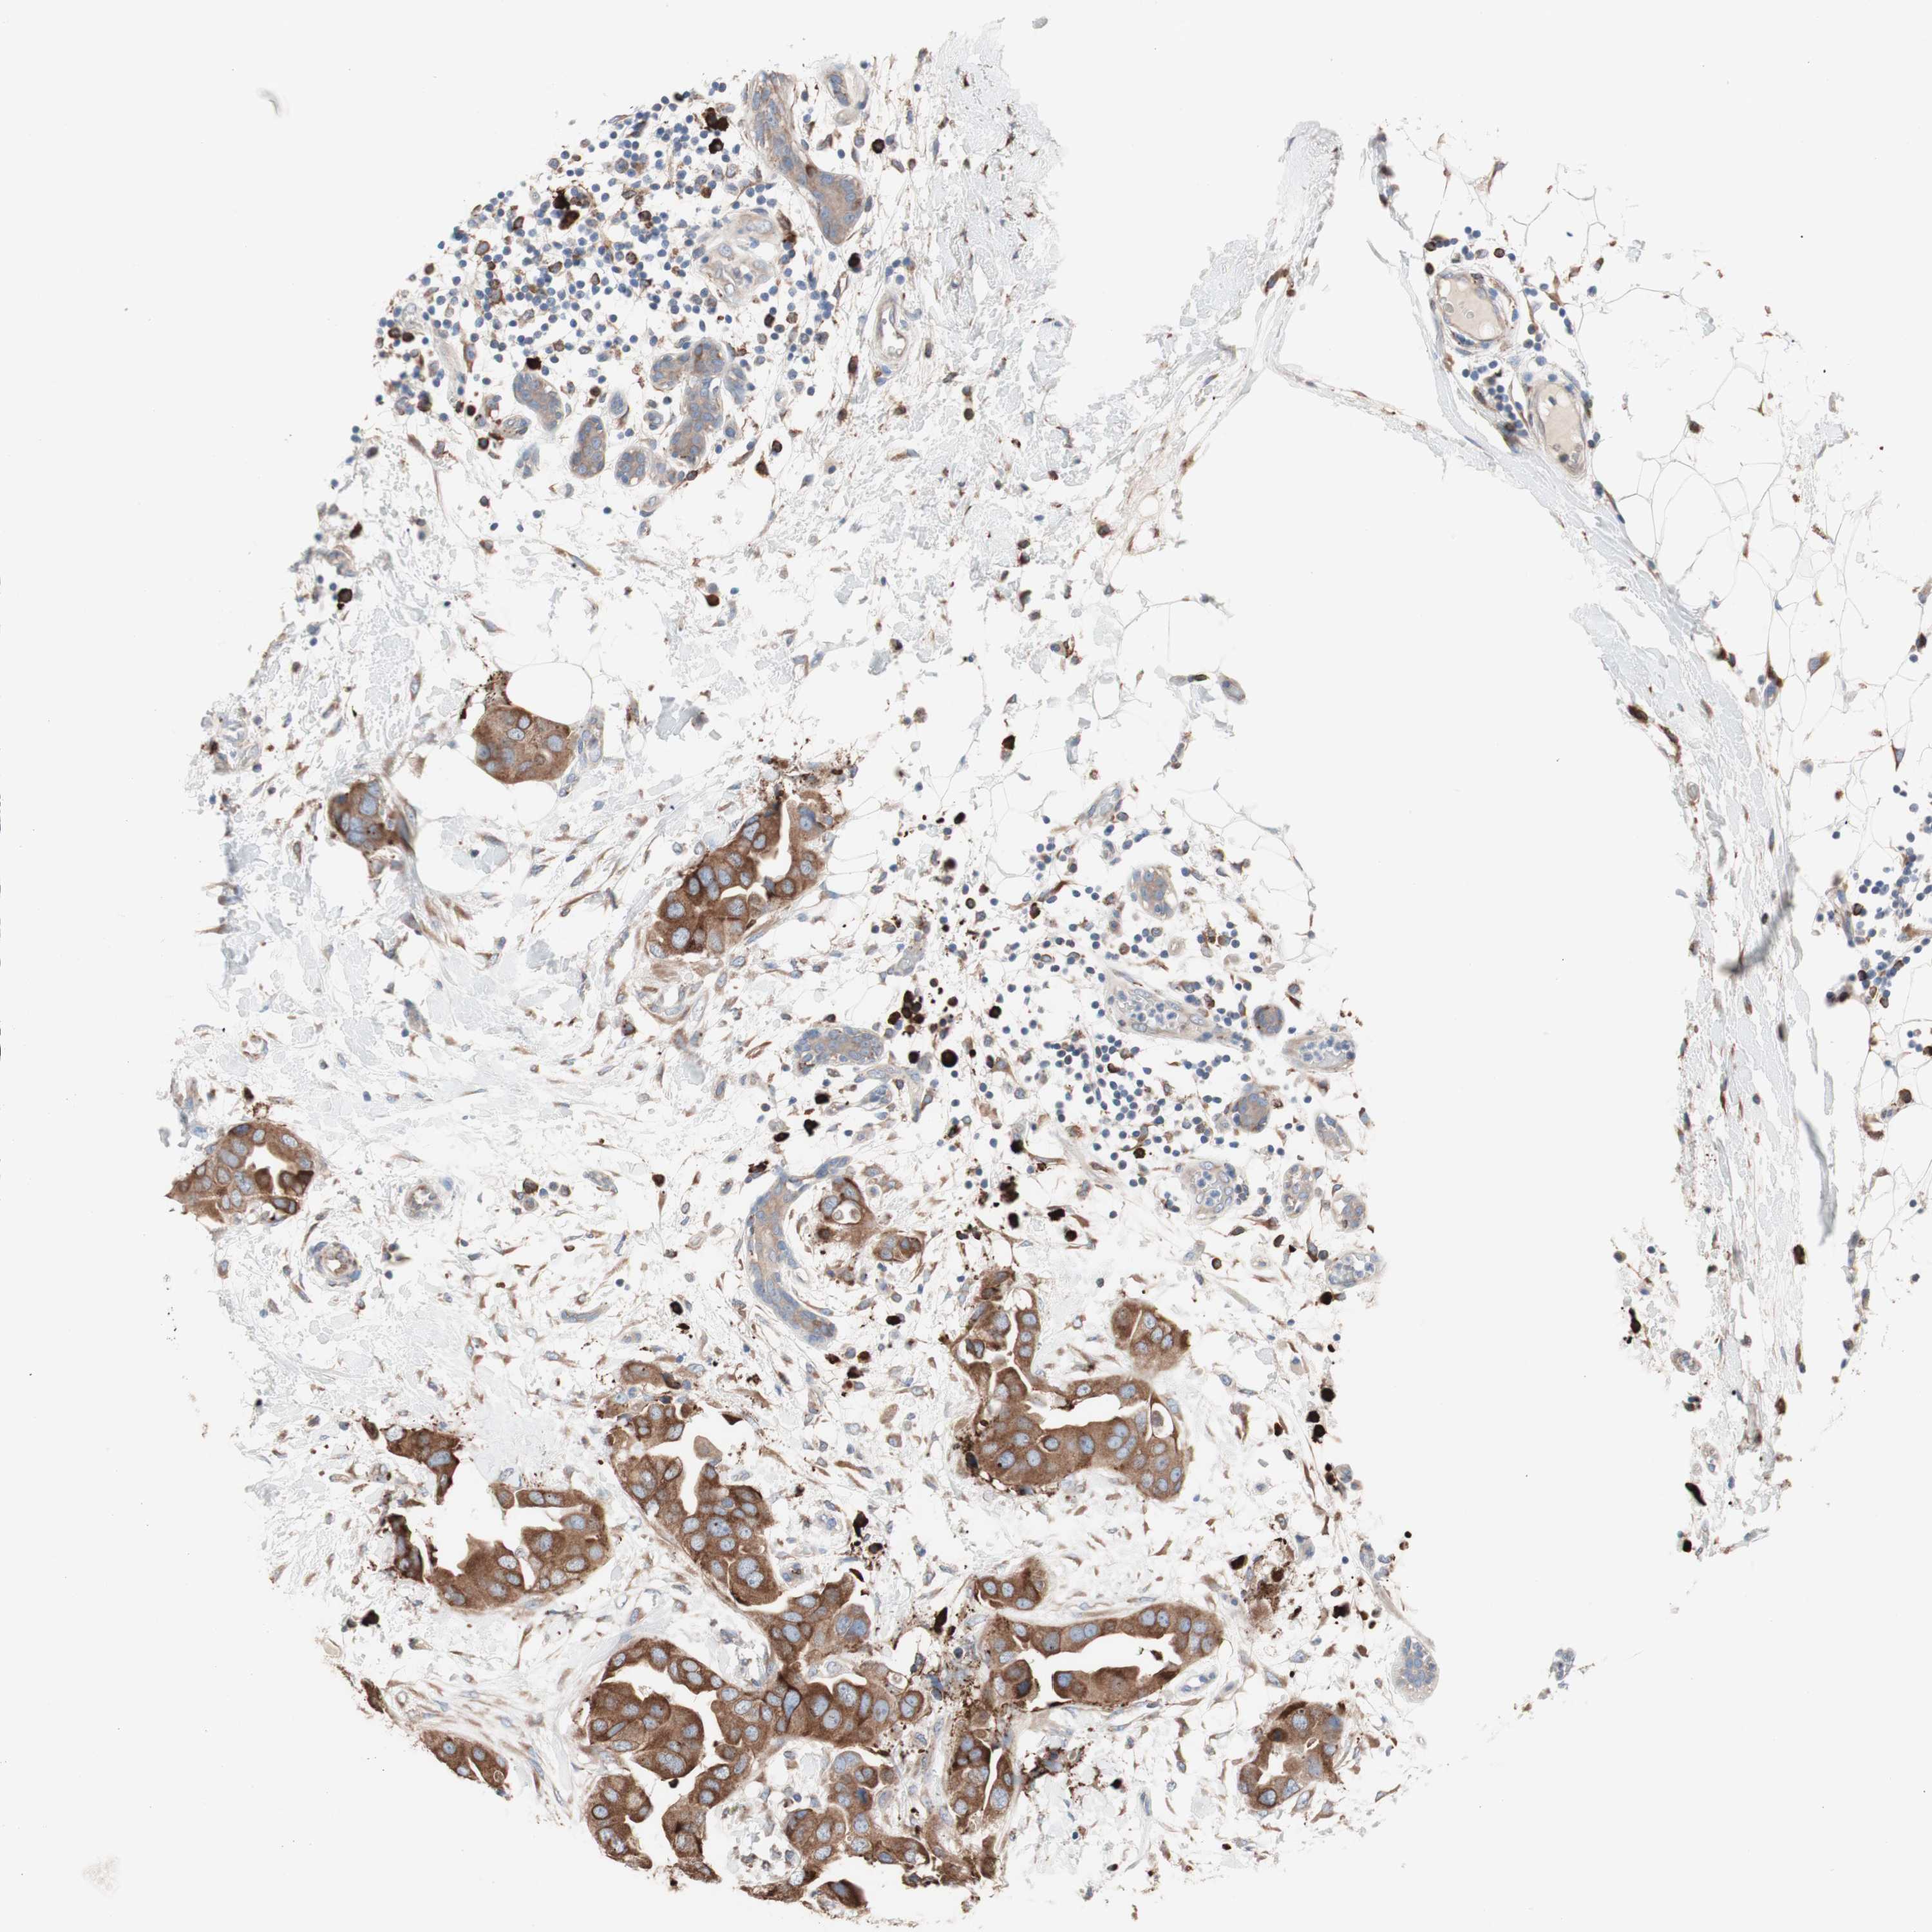

CANCER BREAST CANCER Show tissue menu

BRCA TCGA BRCA VALIDATION PROTEIN EXPRESSION